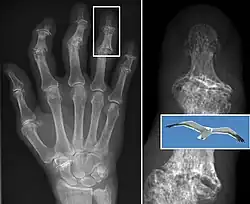

| The formation of hard knobs at the middle finger joints (known as Bouchard's nodes) and at the farthest joints of the fingers (known as Heberden's nodes) is a common feature of osteoarthritis in the hands. | |

In smaller joints, such as at the fingers, hard bony enlargements, called Heberden's nodes (on the distal interphalangeal joints) or Bouchard's nodes (on the proximal interphalangeal joints), may form, and though they are not necessarily painful, they do limit the movement of the fingers significantly. Osteoarthritis of the toes may be a factor causing formation of bunions,[16] rendering them red or swollen.

Diagnosis is made with reasonable certainty based on history and clinical examination.[52][53] X-rays may confirm the diagnosis. The typical changes seen on X-ray include: joint space narrowing, subchondral sclerosis (increased bone formation around the joint), subchondral cyst formation, and osteophytes.[54] Plain films may not correlate with the findings on physical examination or with the degree of pain.[55]

In 1990, the American College of Rheumatology, using data from a multi-center study, developed a set of criteria for the diagnosis of hand osteoarthritis based on hard tissue enlargement and swelling of certain joints.[56] These criteria were found to be 92% sensitive and 98% specific for hand osteoarthritis versus other entities such as rheumatoid arthritis and spondyloarthropathies.[57]

Bone (left) and clinical (right) changes of the hand in osteoarthritis